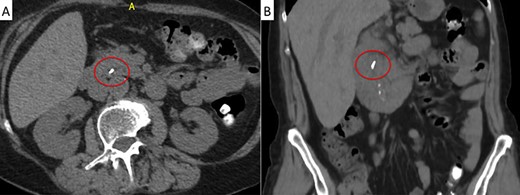

A 71-year-old woman with a history of LC for acute cholecystitis 6 years earlier was admitted with right upper quadrant abdominal pain, jaundice and fever. On admission, her vital signs were body temperature 38.2°C, pulse rate 96/min, respiration rate 21/min, blood pressure 100/60 mmHg and SpO2 98%. Her laboratory tests showed leukocytosis (19.200/ml), an erythrocyte sedimentation rate of 25 mm/h, C-reactive protein of 26 mg/l and altered liver function tests with cholestatic pattern: total bilirubin 4.95 mg/dl (normal up to 1.2), direct bilirubin 4.18 mg/dl, alkaline phosphatase 1083 IU/l (normal up to 150), gamma-glutamyl transferase 169 IU/l (normal up to 45), aspartate transaminase 281 IU/l (normal up to 40) and alanine transaminase 330 IU/l (normal up to 41). Serum amylase and lipase were normal. Abdominal ultrasound showed biliary tract dilatation but not obstructive cause, with a maximum diameter of the CBD of 17.6 mm. A subsequent magnetic resonance cholangiopancreatography (MRCP) found a filling defect in the distal CBD (Fig. 1). ERCP extraction was attempted, but it was impossible to progress the catheter due to an irregular distal bile duct stenosis. An abdominal computed tomography (CT) scan was therefore performed and showed a foreign body with radiopaque characteristics in the distal CBD consistent with a metallic clip (Fig. 2). Given that the object could not be removed by ERCP due to technical difficulties in biliary cannulation, laparoscopic bile duct exploration was decided.

Magnetic resonance cholangiopancreatography (MRCP) showing a filling defect in the distal bile duct (red circle).

Abdominal CT scan. A metallic artifact is observed in the distal common bile duct (red circle) in axial (A) and coronal (B) planes.